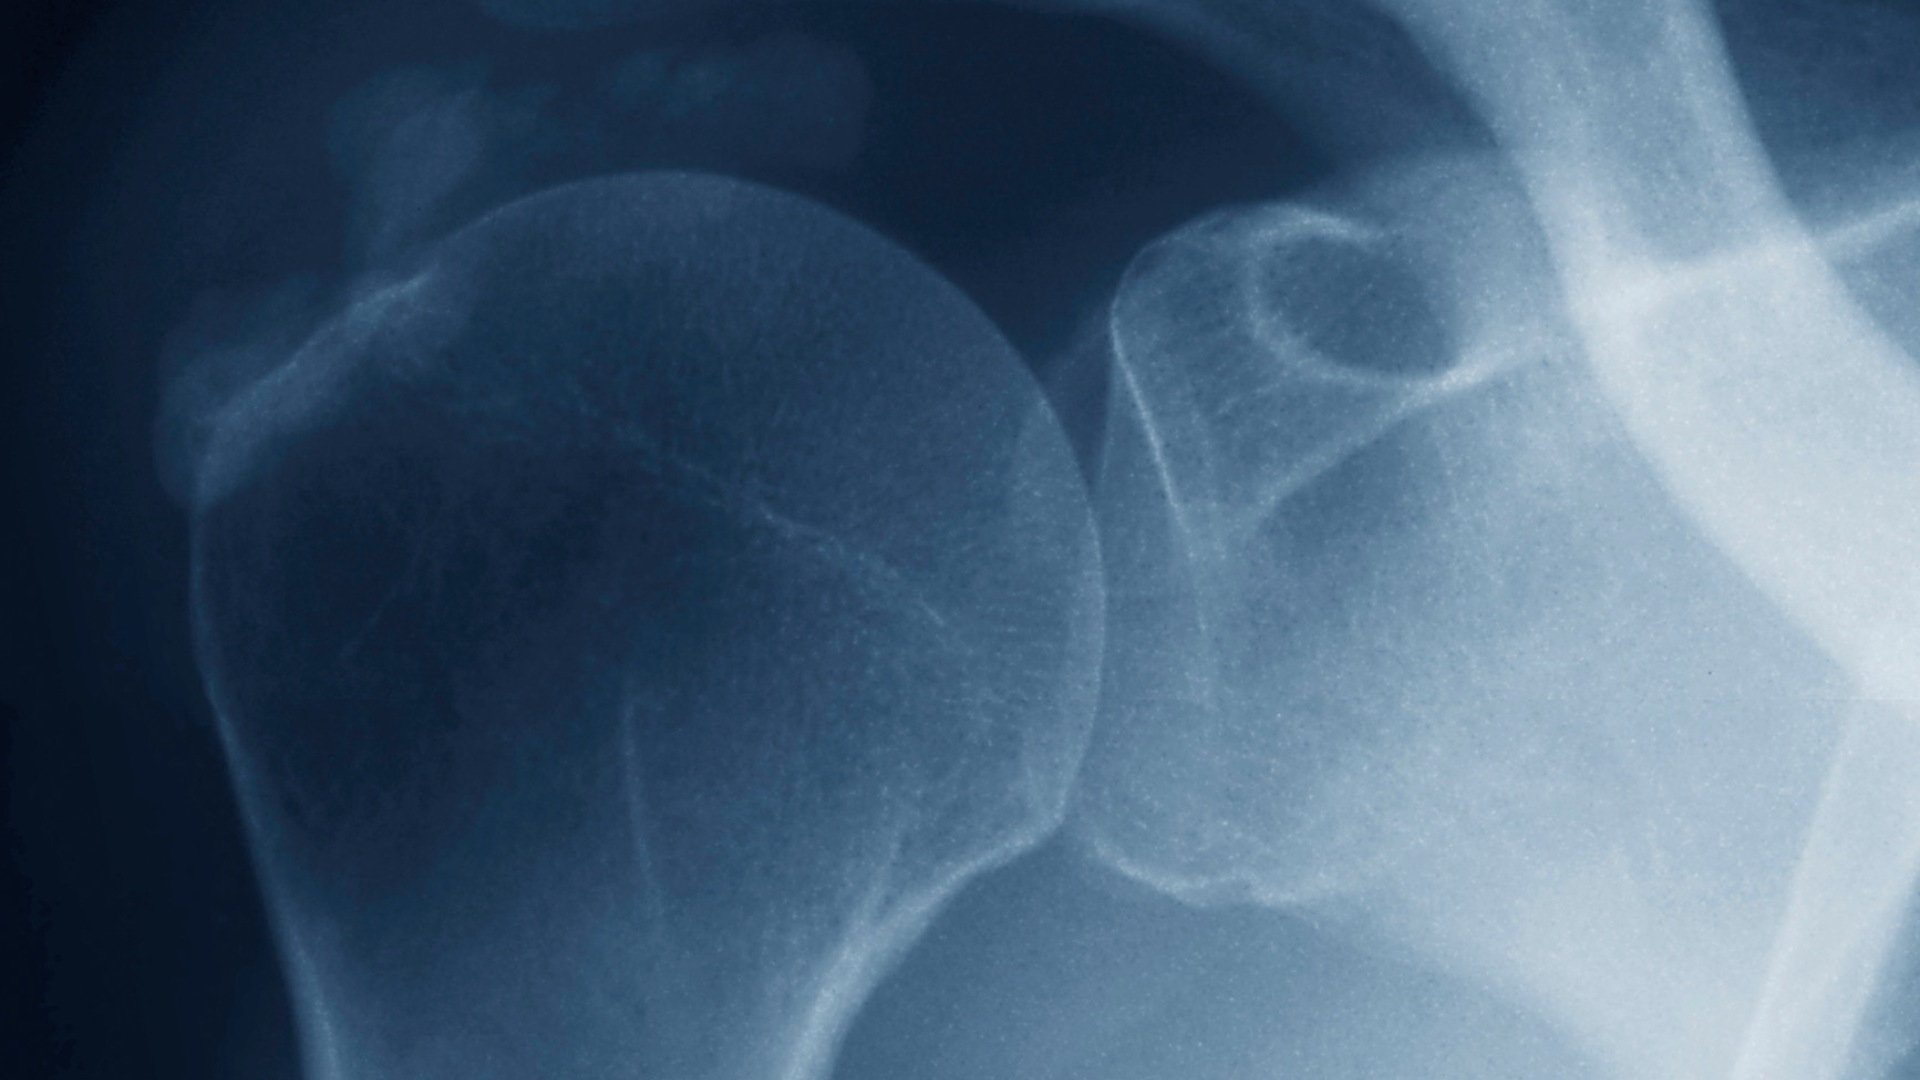

Calcific tendinitis is a type of tendinopathy, or disorder of the tendons. Tendons are connective tissues that attach muscles to bones. Calcific tendinitis of the shoulder occurs when small calcium crystals, called calcium hydroxyapatite, form inside the structure of a tendon. The location of these deposits is most often in the rotator cuff muscles of your shoulder.

Statistically, calcific tendinitis affects adults most commonly between 30 and 60 years of age. Women are roughly twice as likely as men to develop symptoms of calcific tendinitis. Imaging studies show calcium deposits in 2.7% to 20% of shoulders, and the supraspinatus tendon is most frequently involved.